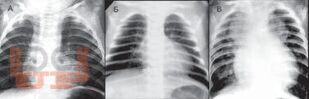

Книга посвящена одному из важнейших разделов детской кардиологии - врожденным порокам сердца. В общей части рассмотрены особенности нормального кровообращения у плода и новорожденного, а также его изменения при врожденной патологии сердца; кроме того, читатель знакомится со специальной терминологией. В разделе частной патологии подробно представлены все основные пороки, встречающиеся в практике детских врачей, алгоритмы их диагностики, современные возможности терапевтического и хирургического лечения; изложены вопросы послеоперационного наблюдения за пациентами. Издание содержит более 140 рисунков и схем, иллюстрирующих ключевые расстройства гемодинамики, методы исследования сердца и наиболее распространенные операции.

Изображения 84